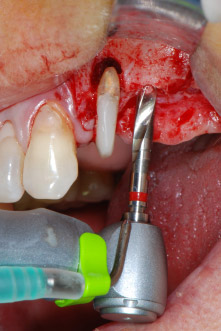

Im folgenden Schritt wurde das jeweilige Implantatbett an den Positionen 25 und 26 mit rotierenden Instrumenten in einem Winkelstück mit einem Übersetzungsverhältnis von 20:1 (WS-75 L G, W&H) und einem vor Kurzem aktualisierten leistungsstarken Implantatmotor präpariert (Implantmed, W&H) (Abb. 8 und 19).

Die Implantatlager wurden mit einem neuen Implantatmotor in Verbindung mit einem speziell für Oralchirurgie und Implantologie konzipierten Winkelstück aufbereitet.

Das Übersetzungsverhältnis von 20:1 und das hohe Drehmoment des Implantatmotors von bis zu 6,2 Ncm (bis zu 80 Ncm am rotierenden Instrument) ermöglichen es, bei geringer Geschwindigkeit Implantatlager zu präparieren, Implantate einzudrehen und bei dichtem Knochen Gewinde vorzuschneiden.